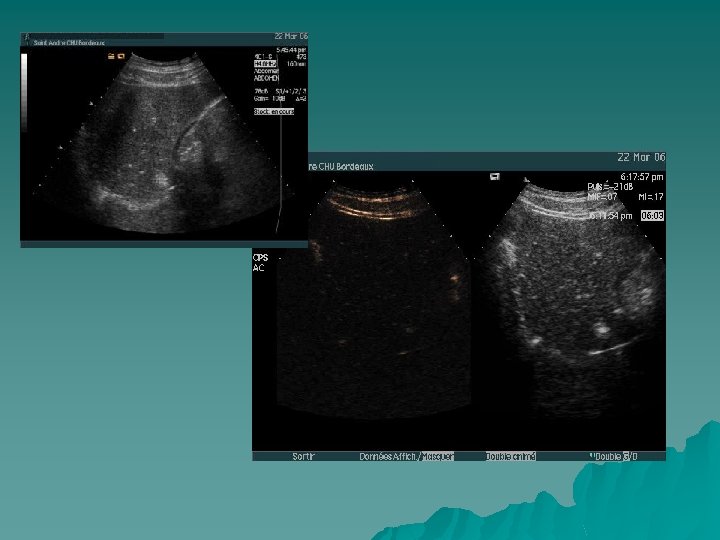

Bilan de K du sein

US PCUS phase tardive